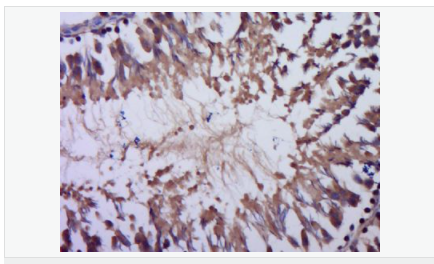

產(chǎn)品應(yīng)用WB=1:500-2000 ELISA=1:5000-10000 IHC-P=1:100-500 (石蠟切片需做抗原修復(fù))

產(chǎn)品介紹This gene encodes a polypeptide hormone precursor that undergoes extensive, tissue-specific, post-translational processing via cleavage by subtilisin-like enzymes known as prohormone convertases. There are eight potential cleavage sites within the polypeptide precursor and, depending on tissue type and the available convertases, processing may yield as many as ten biologically active peptides involved in diverse cellular functions. The encoded protein is synthesized mainly in corticotroph cells of the anterior pituitary where four cleavage sites are used; adrenocorticotrophin, essential for normal steroidogenesis and the maintenance of normal adrenal weight, and lipotropin beta are the major end products. In other tissues, including the hypothalamus, placenta, and epithelium, all cleavage sites may be used, giving rise to peptides with roles in pain and energy homeostasis, melanocyte stimulation, and immune modulation. These include several distinct melanotropins, lipotropins, and endorphins that are contained within the adrenocorticotrophin and beta-lipotropin peptides. Mutations in this gene have been associated with early onset obesity, adrenal insufficiency, and red hair pigmentation. Alternatively spliced transcript variants encoding the same protein have been described. [provided by RefSeq, Jul 2008].